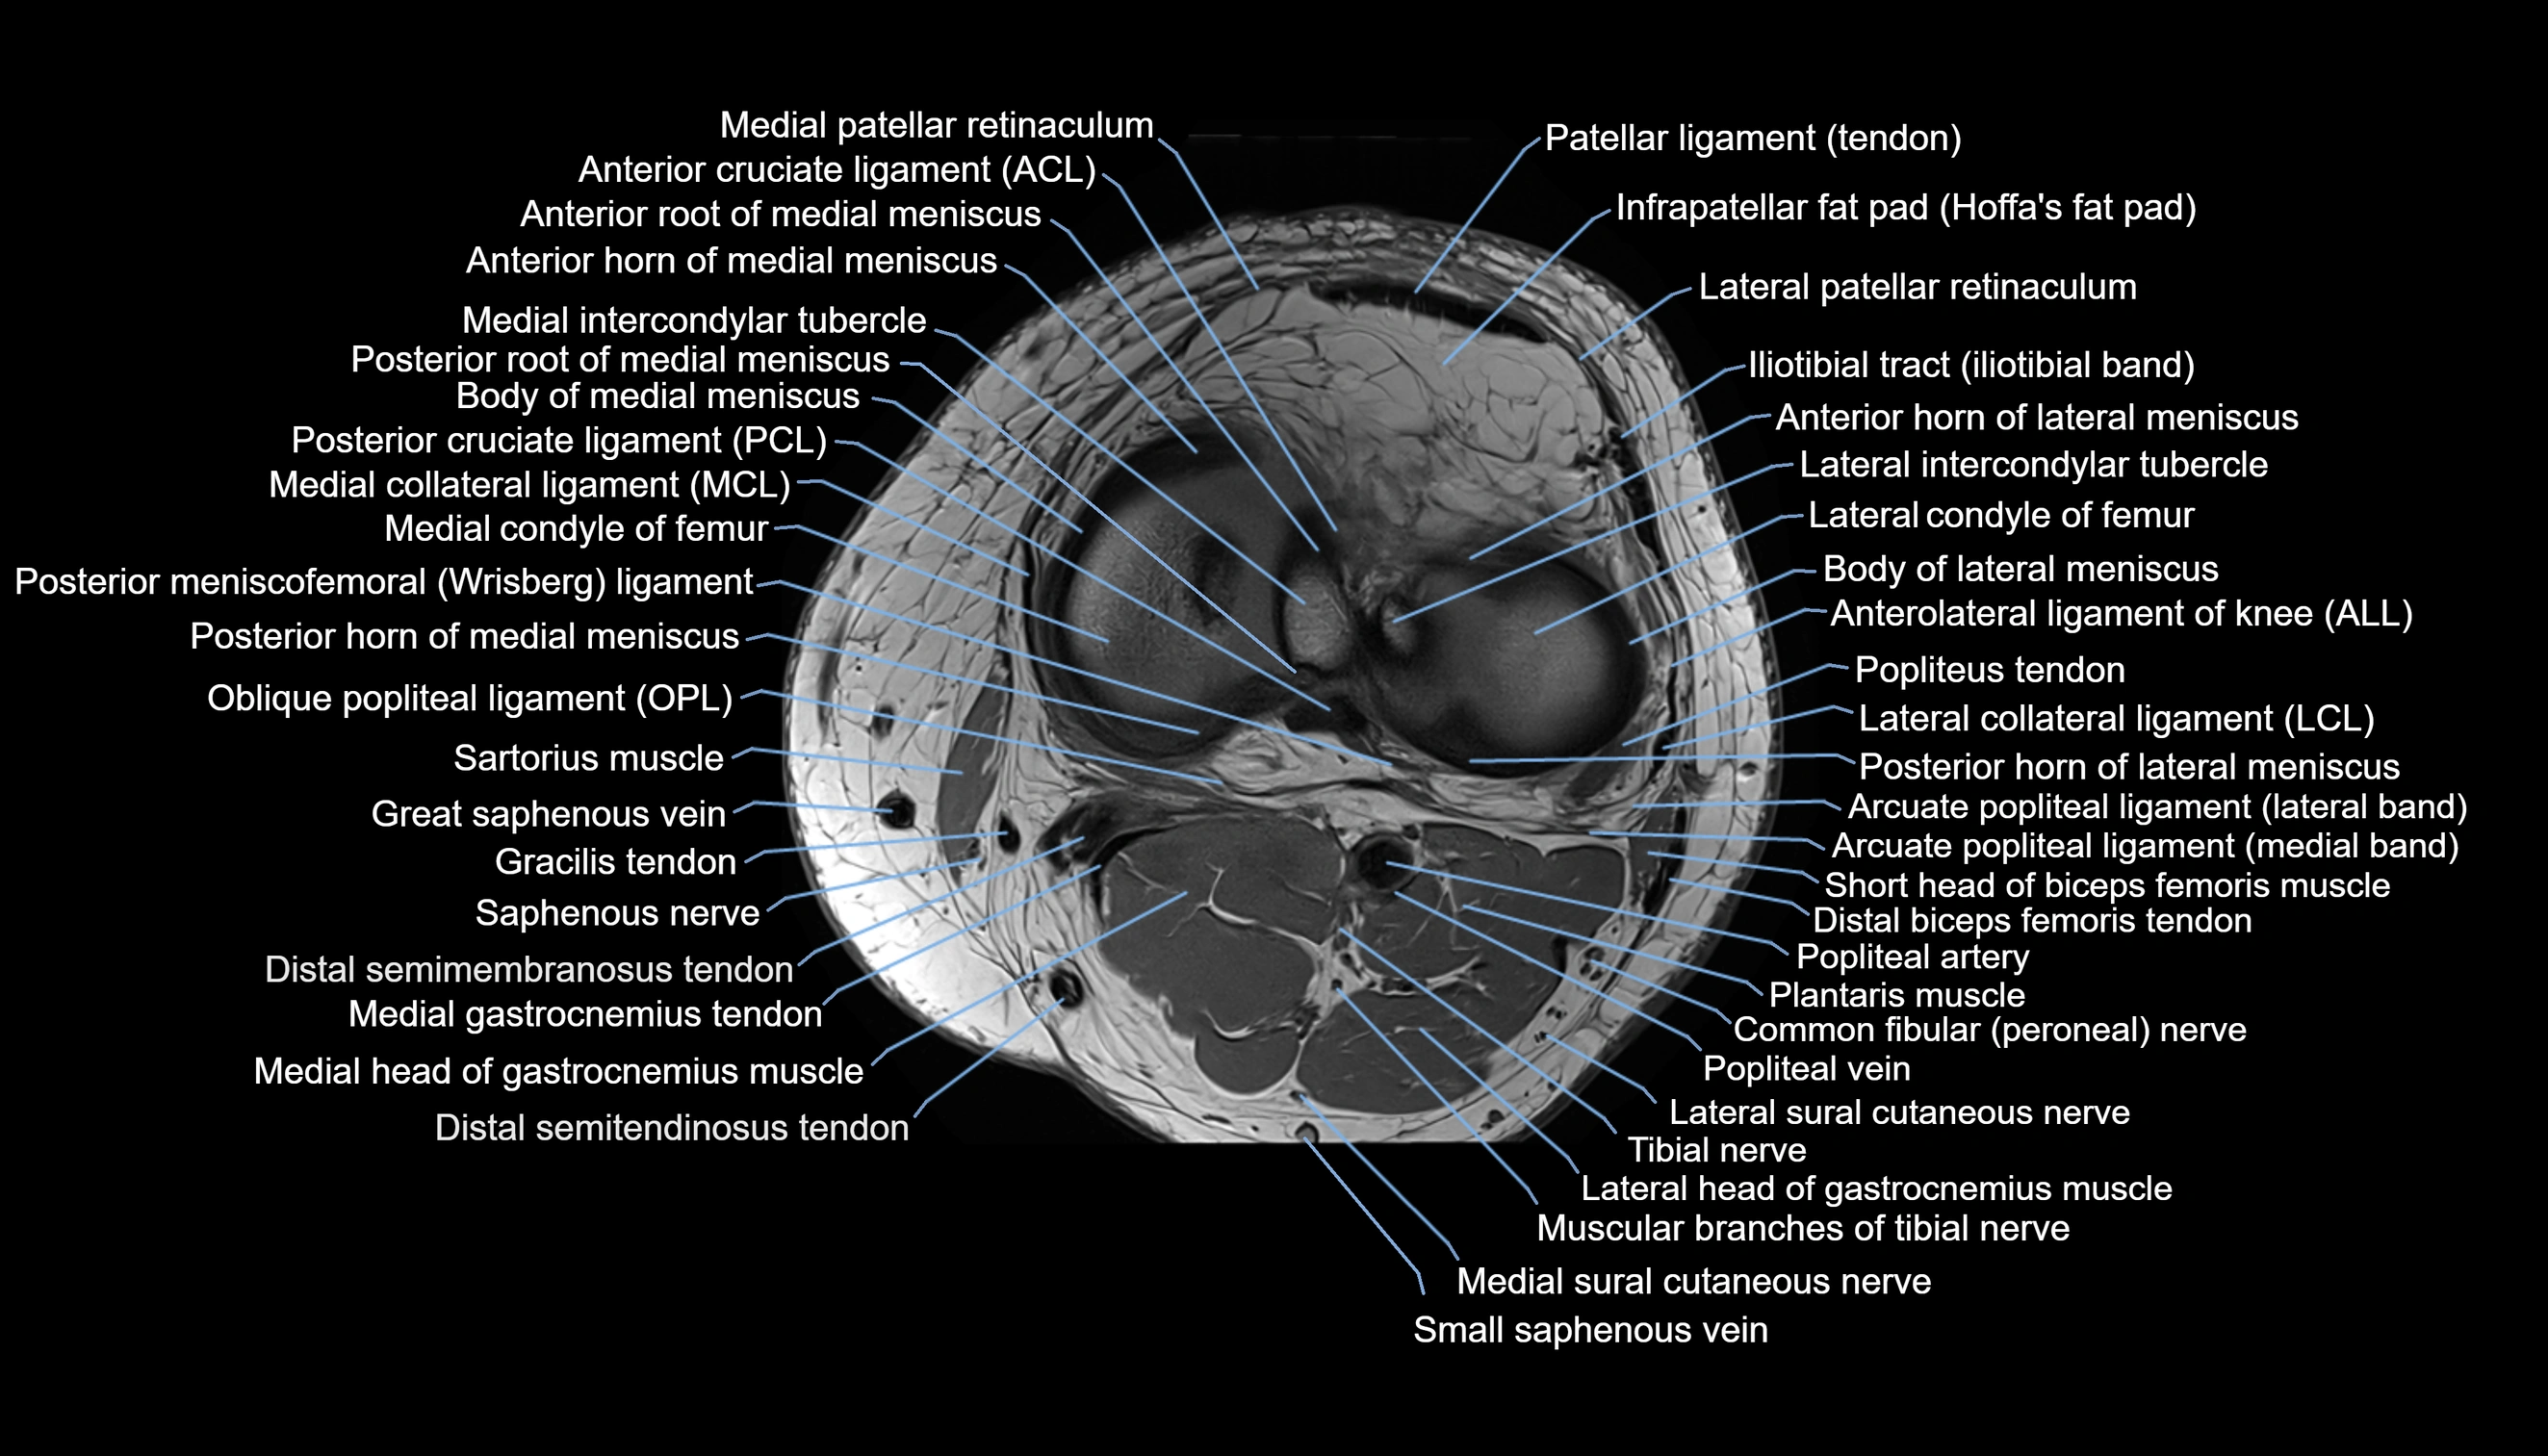

- Anterior cruciate ligament

- Anterior horn of lateral meniscus

- Anterior horn of medial meniscus

- Anterior root of lateral meniscus

- Anterior root of medial meniscus

- Anterolateral ligament of knee

- Arcuate popliteal ligament

- Body of lateral meniscus

- Body of medial meniscus

- Common fibular nerve

- Lateral collateral ligament

- Lateral condyle of femur

- Lateral intercondylar tubercle

- Lateral meniscus

- Lateral patellar retinaculum

- Lateral patellofemoral ligament

- Lateral sural cutaneous nerve

- Medial collateral ligament

- Medial condyle of femur

- Medial gastrocnemius tendon

- Medial head of gastrocnemius muscle

- Medial intercondylar tubercle

- Medial meniscus

- Medial patellar retinaculum

- Medial sural cutaneous nerve

- Muscular branches of tibial nerve

- Oblique popliteal ligament

- Patella

- Patellar tendon (patellar ligament)

- Plantaris muscle

- Popliteal artery

- Popliteal lymph nodes

- Popliteal vein

- Popliteal–Saphenous perforating veins

- Popliteus muscle

- Popliteus tendon

- Posterior cruciate ligament

- Posterior horn of lateral meniscus

- Posterior horn of medial meniscus

- Posterior meniscofemoral ligament

- Saphenous nerve

- Sartorius muscle

- Small saphenous vein

- Soleus muscle

- Tibial nerve

- Tibial tuberosity